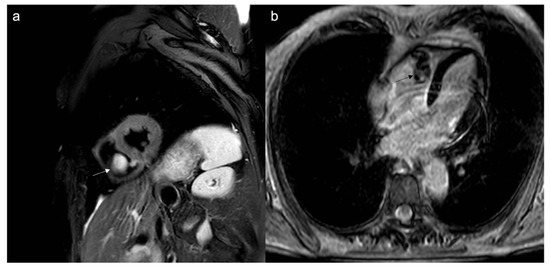

- To recognize fluid content such as a pericardial cyst or myocardial cyst (Figure 3)